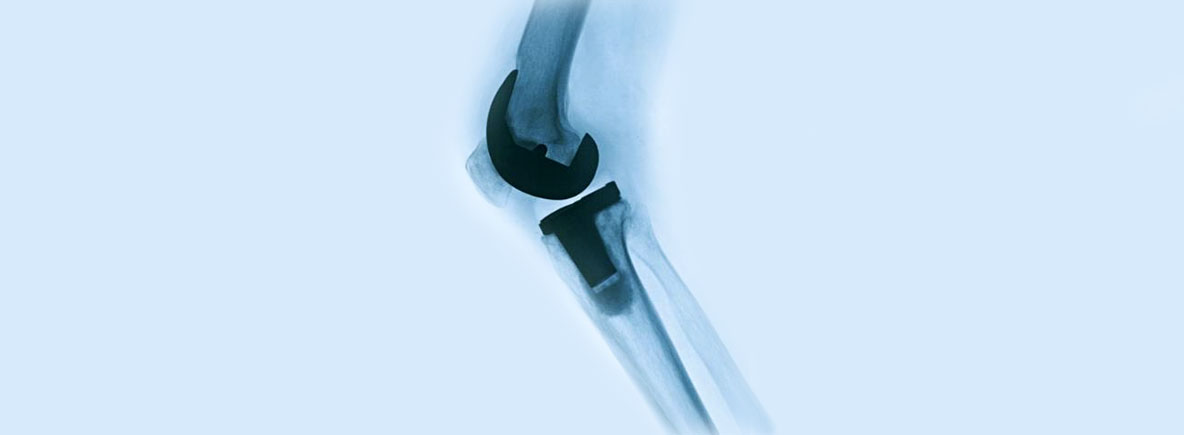

Røntgen kneprotese. Foto

Nasjonalt kvalitets- og kompetansenettverk for leddproteser og hoftebrudd

Kompetansenettverket driver de nasjonale registrene for leddproteser og hoftebrudd. Denne nasjonale tjenesten skal bygge opp og formidle kompetanse på leddproteser og hoftebrudd for å øke kvaliteten og kostnadseffektiviteten av behandlingen.

Målsettingen med registrene er å oppdage dårlige proteser, sementer og operasjonsteknikker så tidlig som mulig, samt å gi kunnskap om epidemiologi. Med økt kompetanse i fagmiljøet og overvåking av effekten av implantater og operasjonsteknikker, forventes kvaliteten på behandlingen å øke. Fagmiljøet i kompetansenettverket driver også Nasjonalt Korsbåndregister og Nasjonalt Barnehofteregister.